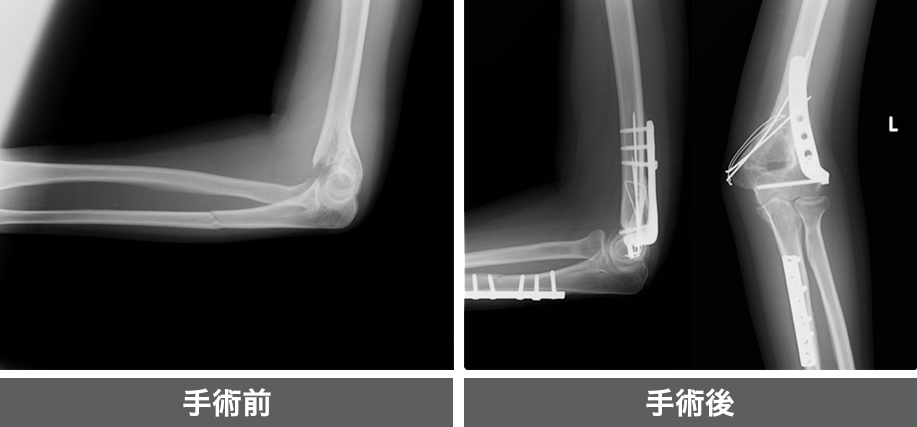

関節周囲に骨が増生してきており、それが原因となり痛みと可動域制限が出現。

原因となる骨を除去し、除痛と可動域改善を図ります。

骨折に対してプレート固定を行います。